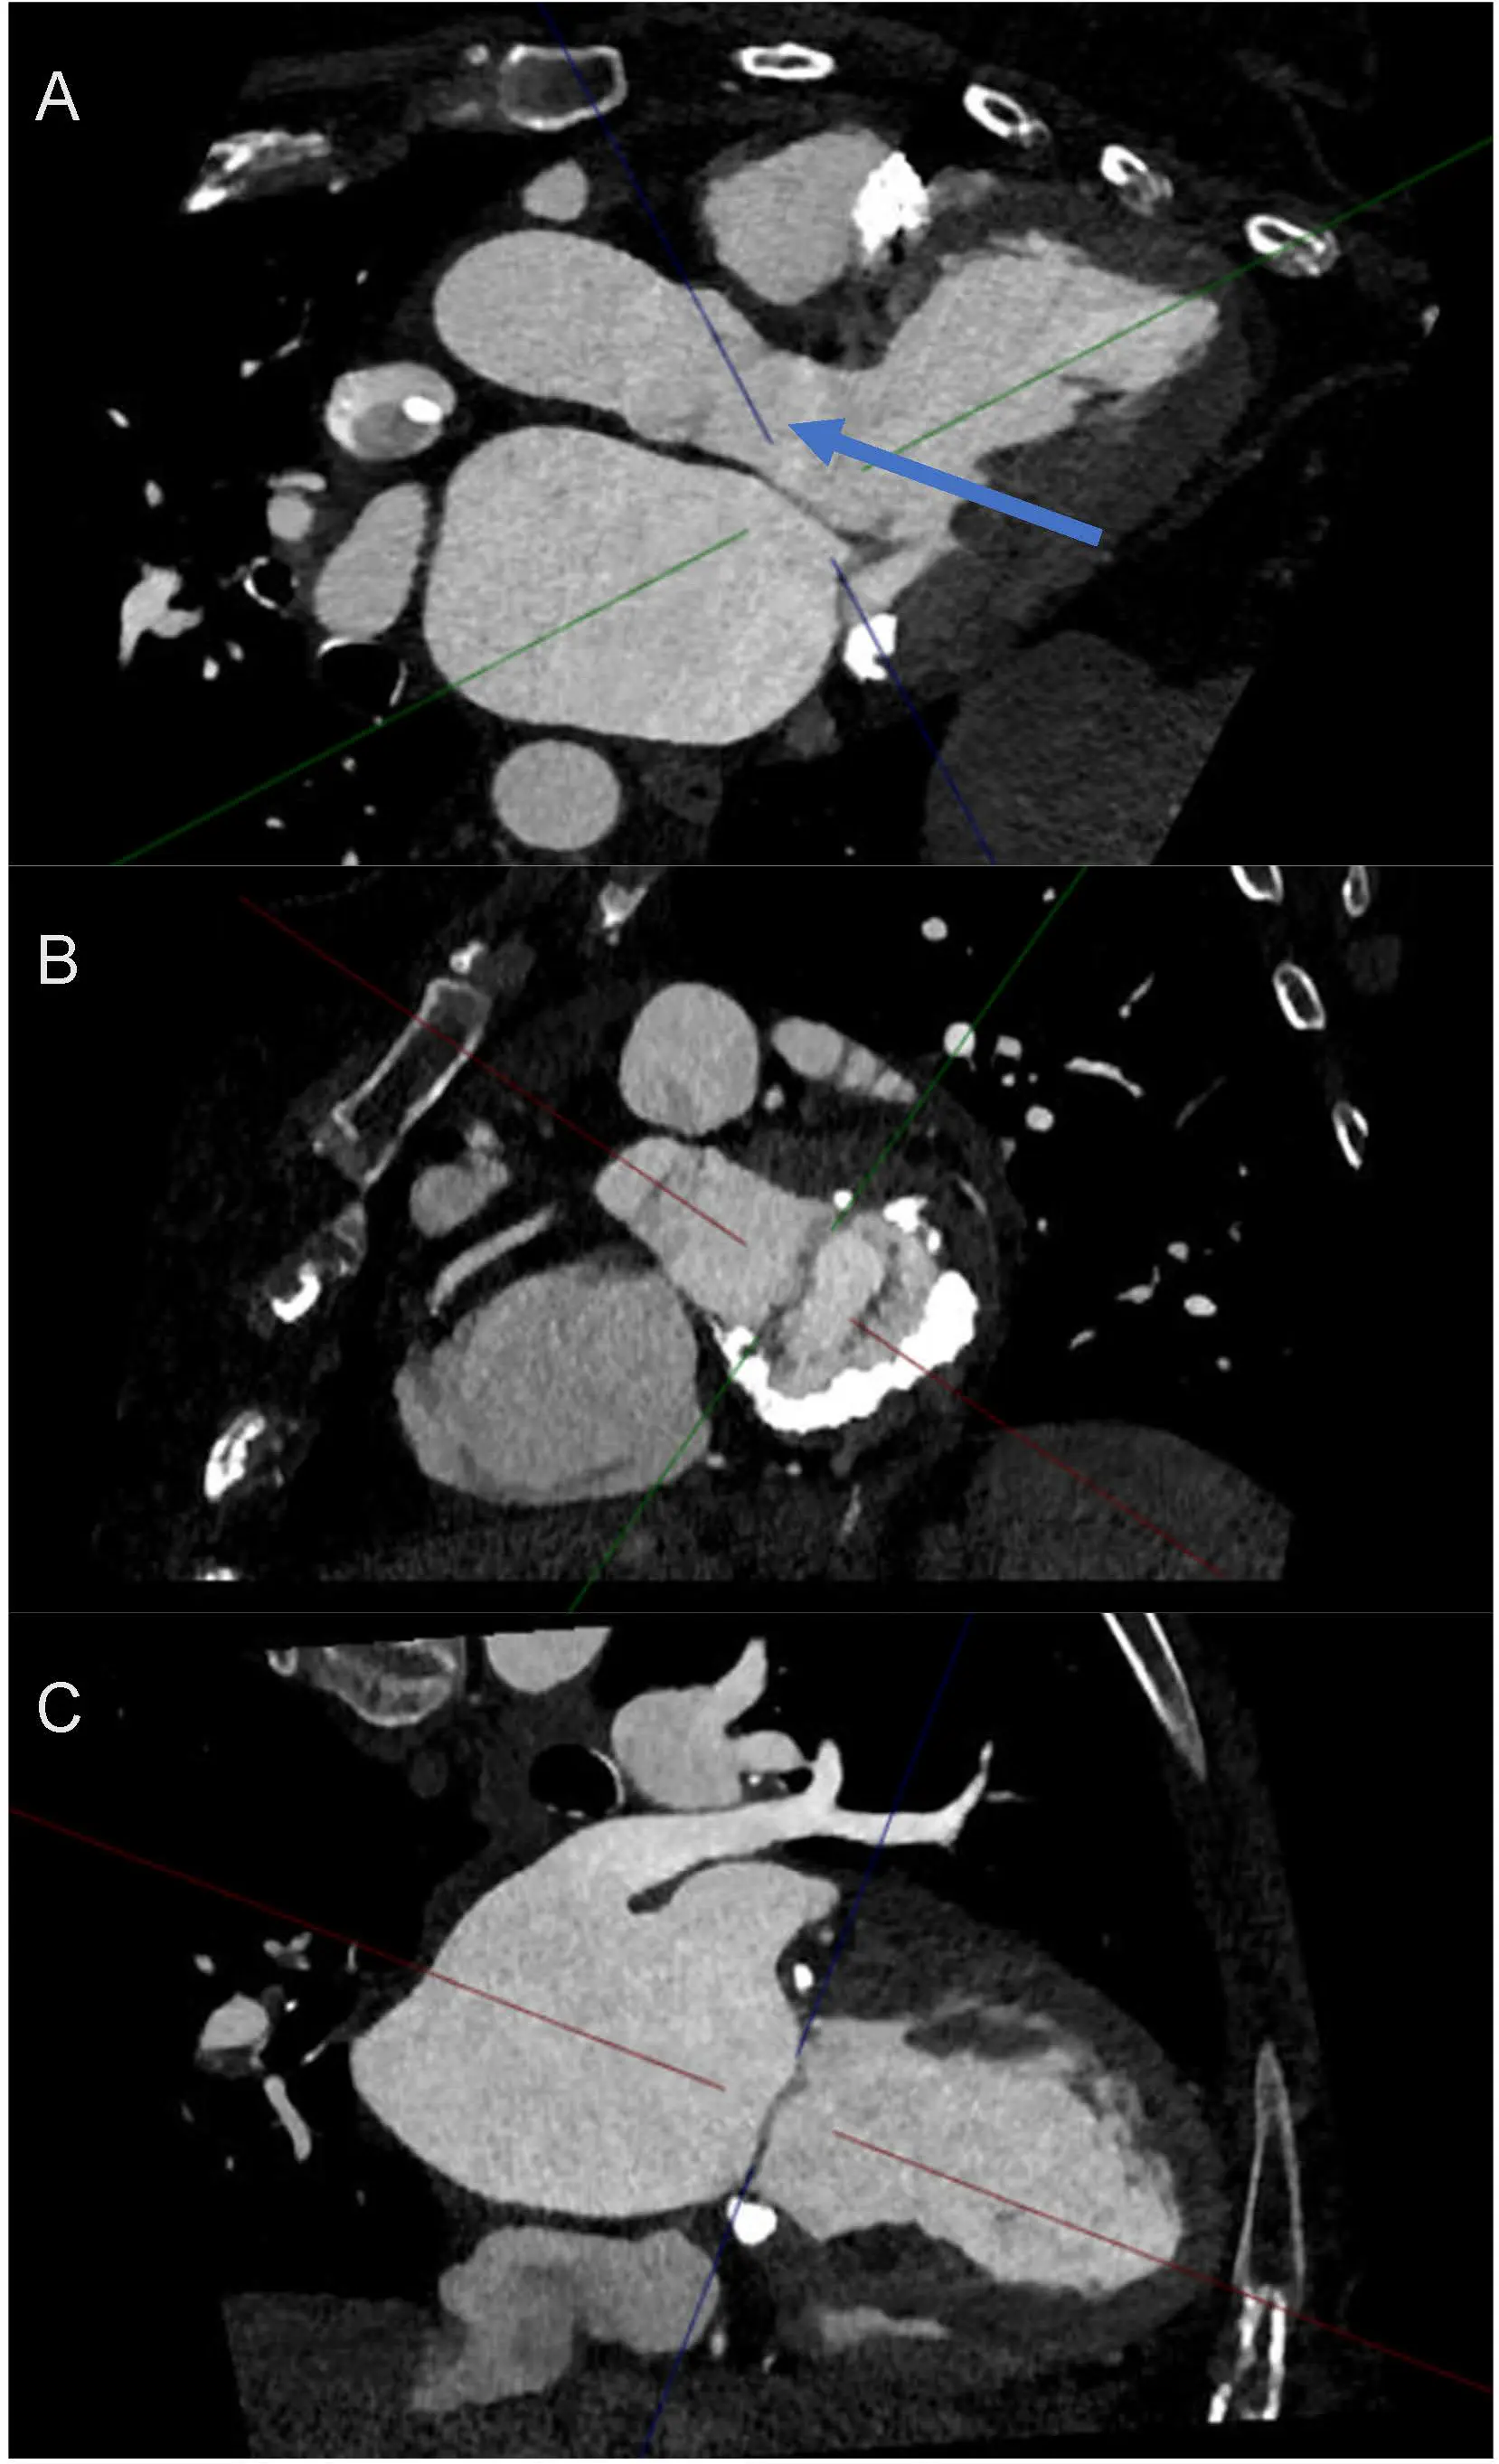

Figure 7. Cardiac Computed Tomography (CT) for Anatomy Evaluation. CT cardiac offers good temporal and spatial resolution for evaluation of cardiac structures and understanding the FMR mechanism and leaflet anatomy (including annulus, any mitral annular calcification, relation to LVOT). This image shows left atrial dilatation and LV dilatation. There is evidence of mitral annular calcification (indicated by the blue arrow).

Figure 8. Use of Cardiac Computed Tomography in Functional Mitral Regurgitation Imaging. (A) 3 chamber view in relation to the mitral valve and the importance of evaluating LVOT (indicated by blue arrow) proximity to mitral valve intervention. (B) Short axis of mitral valve and appreciation of prohibitive anatomy for transcatheter or surgical intervention. This patient has significant mitral annular calcification, but the posterior leaflet still remains mobile. Loss of mitral valve saddle shape is predominantly due to the atrial functional mechanism. (C) 2-chamber view of the left atrium and left ventricle. Colored lines represent multiplanar reformation reference planes (crosshairs) displayed by the CT workstation.

Importantly, CT provides incremental value in phenotyping FMR mechanisms, particularly in differentiating ventricular from atrial functional MR. In VFMR, CT readily demonstrates LV dilation, papillary muscle displacement, leaflet tethering, and increased tenting geometry [22], whereas AFMR is characterized by marked annular dilatation, annular flattening, and preserved papillary muscle geometry in the setting of normal or near-normal LV size [4]. These distinctions are especially relevant in borderline or mixed phenotypes, where accurate mechanistic classification directly informs downstream management strategies.